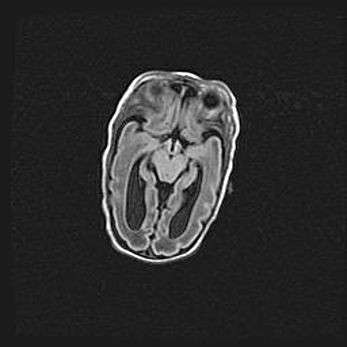

Неполная лизэнцефалия (пахигирия). Открытая гидроцефалия.

Возраст: 17 дней

Вес: 3110 г

Пол: мужской

Окружность головы: 33,5 см

Срок гестации: 35-36 недель

Лизэнцефалия—недоразвитие корковой пластинки и мозговых извилин в результате нарушения миграции нейронов коры. Поверхность мозговых полушарий гладкая. Микроскопически выявляется отсутствие нормальных слоев коры и скопление групп нейронов в подкорковом белом веществе.

Пахигирия—уменьшение числа вторичных извилин. В пораженном полушарии нервные клетки образуют толстый недифференцированный слой с неправильно расположенными нервными волокнами и группами гетеротопных клеток. Нервные клетки незрелые. Белое вещество истончено. При этом нередко аномально развит корково-спинномозговой путь.